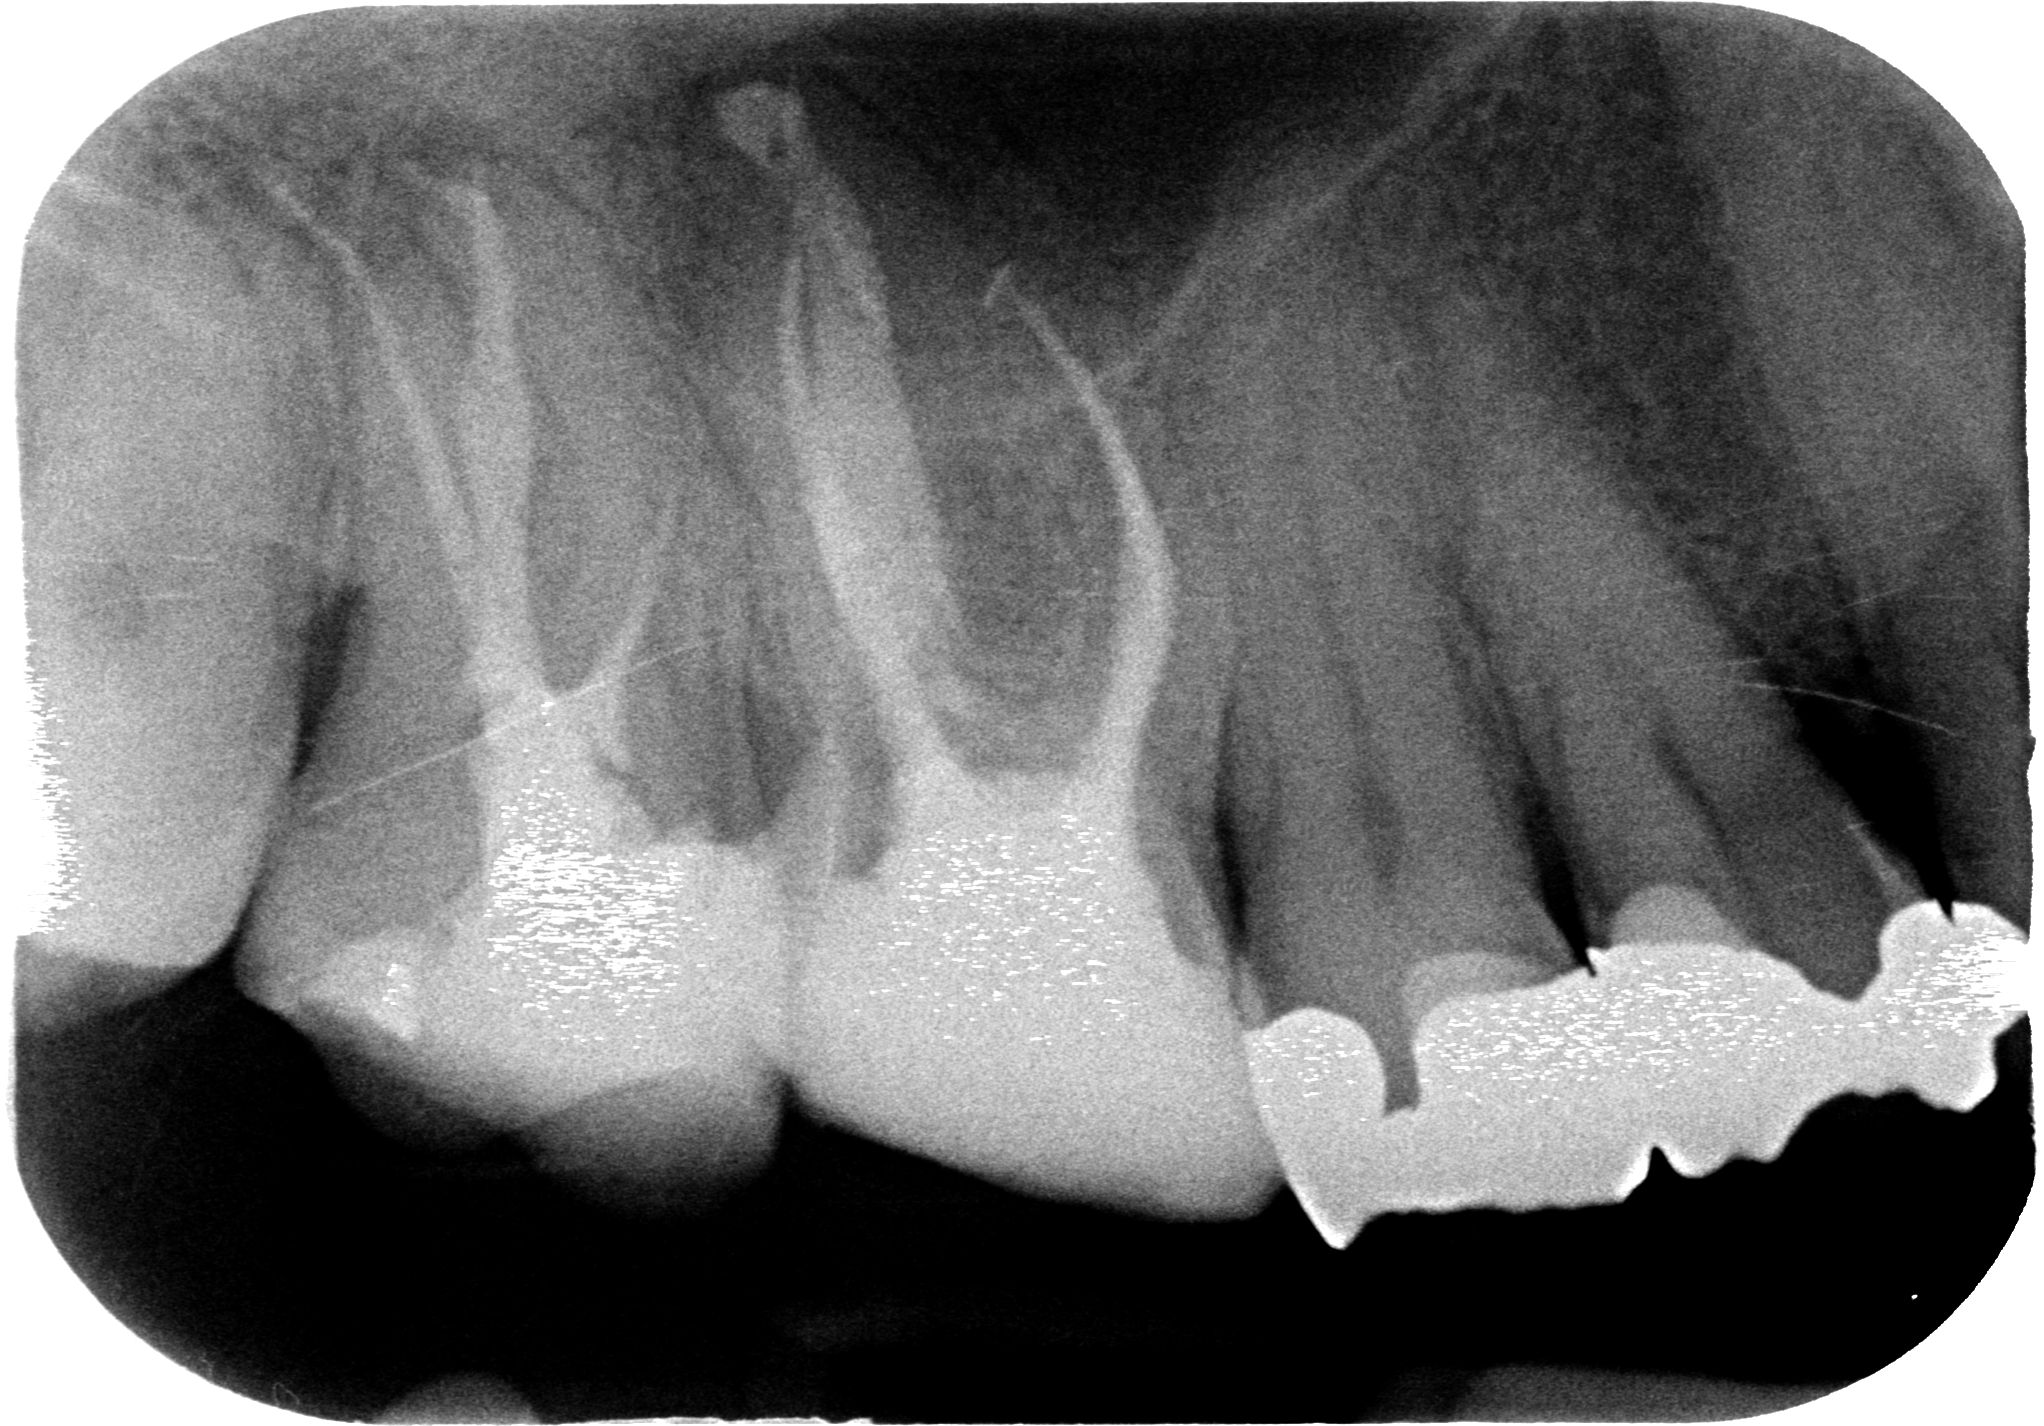

Adesso abbiamo la tac e la commentiamo assieme.

Ripreso il lavoro, con la stessa punta endodontica che ho usato in precedenza mi allargo da dove avevo creato il pozzetto esplorativo in direzione disto-palatina. Teoricamente senza scendere troppo dovrei trovare un canale bello pervio. 15 secondi con la punta endodontica. Prendo un file…Sento cedere…Batticuore…Attacco il rilevatore…Salgo, 12 mm, 14 mm, 16 mm…19 mm! Dlin dlin dlin! Grande! A questo punto sono sicuro che sia il canale giusto, visto che misura quanto il disto-vestibolare, e ne riesco a percepire la curvatura disto-palatina che mi aspettavo.

Il paziente e noi tiriamo un sospiro di sollievo. Dopo questo tentativo per il paziente si apriva lo spauracchio dell’apicectomia che non avrebbe voluto fare e che io stesso avrei faticato a praticare per la posizione sfavorevole.